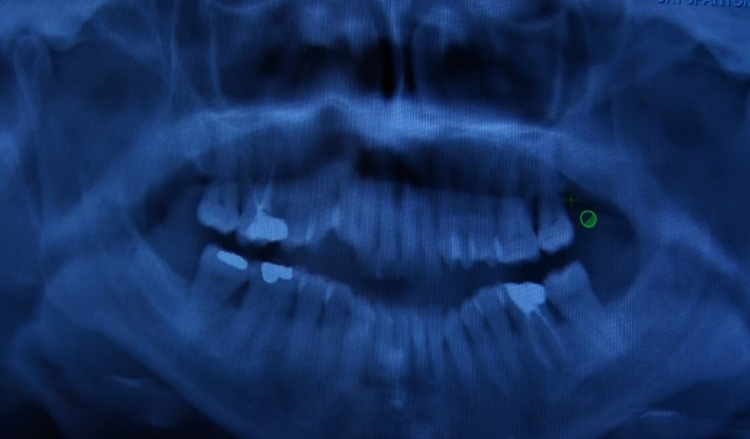

Ağız ve diş sağlığında koruyuculuğun önemine vurgu yapan uzmanlar, diş eti hastalıkları ve neden olabileceği problemlere karşı uyarılarda bulundu. Vatandaşların çoğu zaman kanama, ağrı gibi belirtileri önemsememesinin daha ciddi problemlere neden olabileceğini aktaran Sarıyer Ağız ve Diş Sağlığı Merkezi Periodontoloji(Diş Eti Hastalıkları) Bölümü’nden Uzm. Dt. Ebru Özkan Bütün, sürece ilişkin bilgi verdi.

Uzm. Dt. Ebru Özkan Bütün, "Sağlıklı dişler sağlıklı bir zemin üzerinde var olabiliyor. Diş eti rahatsızlıkları genelde sessiz ilerler. Bize hastalar bir ağrı şikayetiyle değil de daha çok diş etlerinde kanama, diş sallanması ya da diş eti çekilmesi olduğu zamanlarda başvurur. Hatta randevularımızın çoğunu başka diş hekimlerinin yönlendirmesiyle durumun farkına varan hastalar oluşturmakta. Oysa bahsettiğim başvuru nedeni olan o şikayetler hastalığın ileri aşamalarını gösteriyor. Bu nedenle erken teşhis ve tedavi koymak için rutin kontroller diş hekimliğinde çok önemli. Tedavi süreci kişiye özel bizde basit bir diş taşı temizliğiyle de sorunu çözebiliyoruz ama bu ileri cerrahi aşamalara kadar da ilerleyebiliyor. En önemli nokta; kişinin evde uyguladığı ağız hijyeni uygulamaları, rutini. Her zaman söylüyoruz; günde en az 2 kere diş fırçalama, diş ipi kullanımı veya ara yüz fırçası kullanımı, düzenli kontrolleri aksatmamak altın standart. Bunlara uyulduğu sürece durum da kontrol altında olacaktır" dedi.

Sık yapılan hatalara yönelik konuşan Dt. Bütün, "Çok sık karşılaştığımız bir durum var; hastalar diş eti kanadığında fazlaca bastırdım sanarak fırçalamayı azaltıyorlar ya da daha yumuşak fırçalara geçerek yetersiz fırçalamaya başlıyorlar oysaki durum bunun tam tersi. Diş etlerimizin kanaması o bölgeye fırçayı daha çok sürmemiz ve daha etkili temizlememiz için gelen bir sinyaldir. Eğer dişlerimiz kanıyorsa direkt diş hekimimize müracaat etmeliyiz. Periodontal sağlık vücudumuzun genel olarak bütünüyle de ilişkilidir sadece ağzı için önemli değildir. Artık biliyoruz ki diyabetten kalp damar rahatsızlıklarına ya bazı solunum yolu hastalıklarından nörolojik rahatsızlıklara kadar pek çok sistemle ilişkili bulunmuş bu periodontal durumlar. Diş eti kanamaları bazı hastalıkların göstergesi olabiliyor. ‘Kaplama yaptırdım o yüzden fırçalamıyorum’ olayı var. Kişi, dişler kaplandığı için onları temizlemeyeceğini düşünüyor aksine araları daha iyi temizlemeliyiz, normal dişlere sahip bir bireydense kaplamalı dişlere sahip bireyler ara yüz temizliğine çok önem vermeli, gerekirse ağız duşu uygulamalı. Kaplamalı dişler ya da ağızda ilave bir şeyleri; aparey, tel varsa onların da dikkat etmesi gerekiyor. Yaş sınırı tok, genel olarak ağız bakımı yetersizse ve bu temel oluşmuşsa kanama, diş eti rahatsızlıkları ve kemik kaybına kadar ilerleyen şeyler gördüğümüz bir şey" şeklinde konuştu.